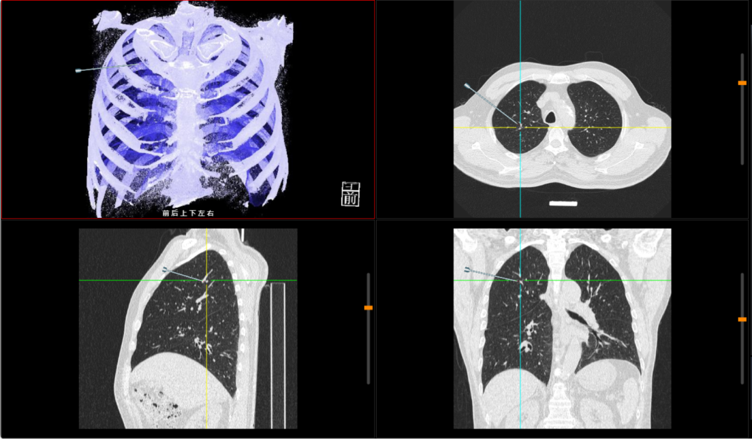

多模态融合手术规划与术后评估方案能支持多种设备类型、多序列及功能像与解剖像融合,提供全面解剖与代谢信息,精准定位病灶,继而完成三维重建、手术路径模拟及入路优化设计,评估血管、神经等重要脏器组织的潜在风险,提升复杂病例手术精度。